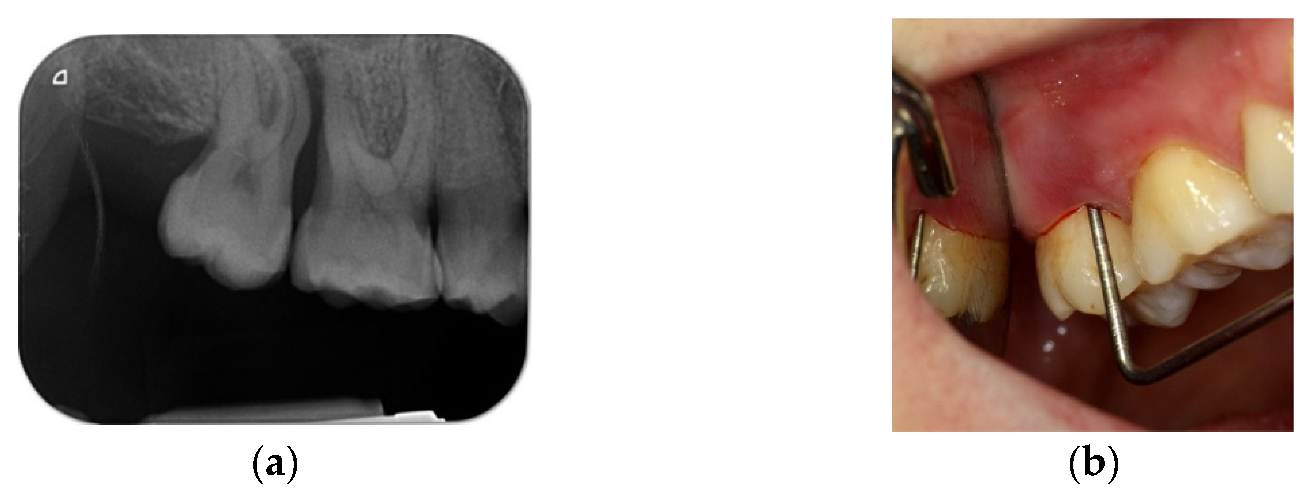

4.1. Clinical Case n.1.